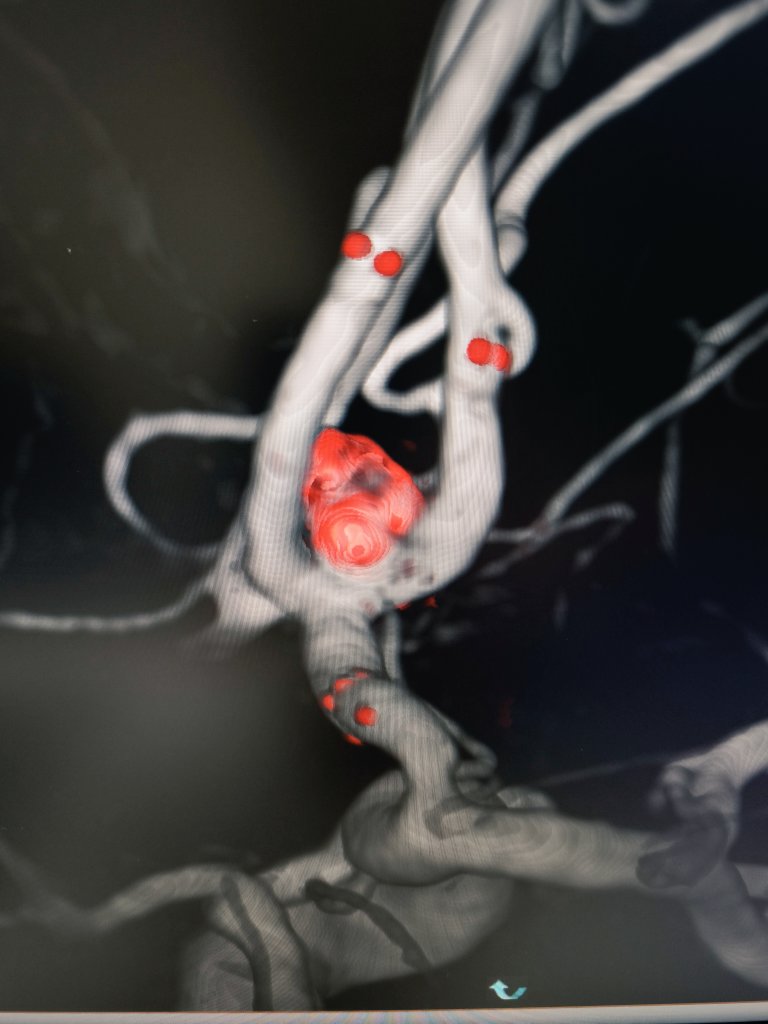

Mycotic (infectious) cerebral aneurysm (CA) resulting from infection of the arterial wall secondary to bacterial endocarditis. Represent < 5% of all CA

We treated it with endovascular glue (NBCA) embolization, complete closure, no deficit

@Sremollo

@IsaRCaamano